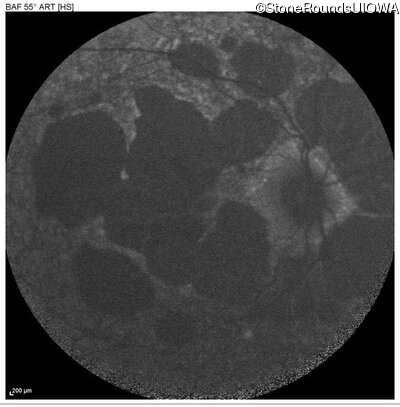

AR Stargardt Disease (IIA)

Age at visit: 51 years

This 51 year old woman first experienced some abnormality in her distance vision when she was 27 years old. She feels that her vision has been stable since that time.

Diagnosis & molecular findings

Disease Gene Allele 1 variant(s) Allele 2 variant(s) Inheritance mode

AR Stargardt Disease ABCA4 Gly1507Arg GGG>AGG IVS42+1 G>A AR